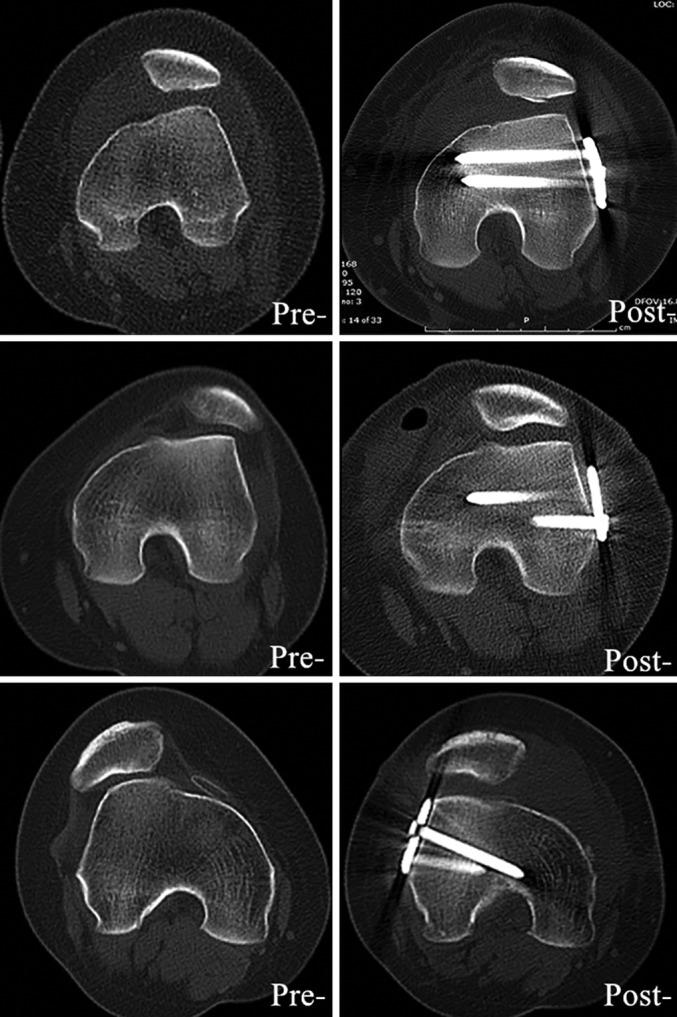

From January 2015 to March 2018, 20 knees in 20 patients (18 female, 2 male) with a mean age of 21 ± 4.2 years (range, 16 to 28 years) were retrospectively reviewed. All patients had undergone femoral derotation osteotomy and medial retinaculum plasty for recurrent patellar dislocation and excessive femoral anteversion angle (FAA > 25°). CT and X-rays were used to assess the correction of the femoral anteversion angle, the tibia tuberosity-trochlear groove (TT-TG) distance, patellar tilt, and the congruence angle following the combinatory operations. Subjective scores, such as Kujala, International Knee Documentation Committee (IKDC), Tegner, and visual analogue scale (VAS) scores, were used to evaluate knee function preoperatively and postoperatively.

No recurrence of patellar dislocation occurred in these patients during an average of 18 months (range, 12 to 23 months) of follow-up. The mean of the FAA was corrected to 15.80° ± 3.58° postoperatively compared with 31.42° ± 4.95° preoperatively (P < 0.001). The TT-TG distance was decreased from 22.17 ± 5.28 mm before surgery to 19.42 ± 4.57 mm after surgery (P = 0.03). The patellar tilt and congruence angle were improved from 30.43° ± 5.30°, 43.30° ± 11.04° to 15.80° ± 3.94°, 16.64° ± 9.98°, respectively (P < 0.001). The Kujala score was improved from 72.4 ± 19.90 before the surgery to 88.2 ± 12.25 after the surgery (P < 0.001). The IKDC score was improved from 70.56 ± 21.44 to 90.78 ± 14.32, and the VAS score was decreased from 4.23 ± 2.11 preoperatively to 1.27 ± 1.08 postoperatively (P < 0.001). No significant difference in Tegner score (5.46 ± 2.49 vs 5.79 ± 1.44) was found before and after the surgery (P = 0.2). Patients younger than 20 years old had lower Kujala (83.46 ± 14.56 vs. 90.84 ± 7.74, P = 0.02) and IKDC (83.49 ± 17.35 vs 92.46 ± 9.28, P = 0.04) scores than those older than 20 years.